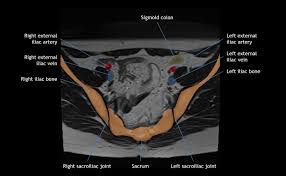

The pelvis is the lower portion of the trunk, located between the abdomen and the lower limbs. Although us, ct and mri may be initially used, pelvic venography is still used to diagnose pvcs and assess the anatomy before treatment is considered. Jun 23, 2021 · the pelvic cavity is described as having two parts: Because of the complexity of this type of injury, a ct scan is commonly ordered for pelvic fractures. This can be done at the same time as ovarian vein/pelvic vein treatment (embolisation) or as a separate procedure if the treatment options need further consideration. In this article, we shall look at the structures of the pelvis, its functions, and the applied anatomy. Abdominal or pelvic adhesions may develop inside the intestine and uterus, or between surfaces of organs and abdominal membrane (peritoneum), thus pulling organs from their original positions, obstructing passage of food and blood supply, causing abdominal or pelvic pain, bloating, constipation, urinary retention, irregular menstrual bleeding. Dec 31, 2009 · surgery stabilizes the injured pelvic ring, restores normal anatomy, provides patient comfort and allows rehabilitation.

It connects the axial skeleton to the lower limbs. Although us, ct and mri may be initially used, pelvic venography is still used to diagnose pvcs and assess the anatomy before treatment is considered. There is a false pelvis that spans the region below the iliac crest and above the arcuate line (pectinate line, anteriorly) and there is a true pelvis that begins below the arcuate line. Types of surgery recommended displaced (misaligned) pelvic fractures may be stabilized by either internal or external fixations (after accurate realignment of the bone fracture fragments or dislocation sites). The pelvis's frame is made up of the bones of the pelvis, which connect the axial skeleton to the femurs, and therefore acts in weight bearing of the upper body. In this article, we shall look at the structures of the pelvis, its functions, and the applied anatomy. The main focus of this article will be the pelvic floor muscles. The pelvis is the lower portion of the trunk, located between the abdomen and the lower limbs. The pelvic inlet or superior aperture of the pelvis is a planar surface which defines the boundary between the pelvic cavity and the abdominal cavity (or, according to some authors, between two parts of the pelvic cavity, called lesser pelvis and greater pelvis). This can be done at the same time as ovarian vein/pelvic vein treatment (embolisation) or as a separate procedure if the treatment options need further consideration. Jun 23, 2021 · the pelvic cavity is described as having two parts: Dec 31, 2009 · surgery stabilizes the injured pelvic ring, restores normal anatomy, provides patient comfort and allows rehabilitation. Because of the complexity of this type of injury, a ct scan is commonly ordered for pelvic fractures.